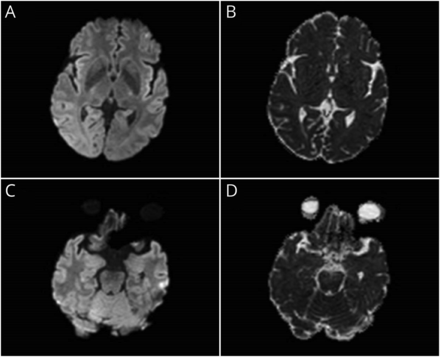

我们与轴向削减显示基底神经节(A和B)和内侧颞叶(C和D) fluid-attenuated反转恢复(天赋)的MRI和18F-FDG-PET。摄影图像显示突出的葡萄糖代谢亢进在双边基底神经节(B,红色箭头)。天赋的图像显示微妙hyperintensities在内侧颞叶(C,黄色箭头)。

大多数anti-LGI1脑炎病例表现为认知功能障碍、精神症状,或癫痫发作。自主功能障碍很少触发器及时anti-LGI1脑炎的诊断。1我们进行了anti-LGI1抗体测试,由于特征正发现。这种情况下说明基底神经节和内侧颞叶代谢亢进anti-LGI1脑炎是两个不同的目标,虽然可以找到类似的发现在其他类型的自身免疫性脑炎(例如,anti-NMDA anti-IgLON5)或自身免疫性舞蹈病。2,3